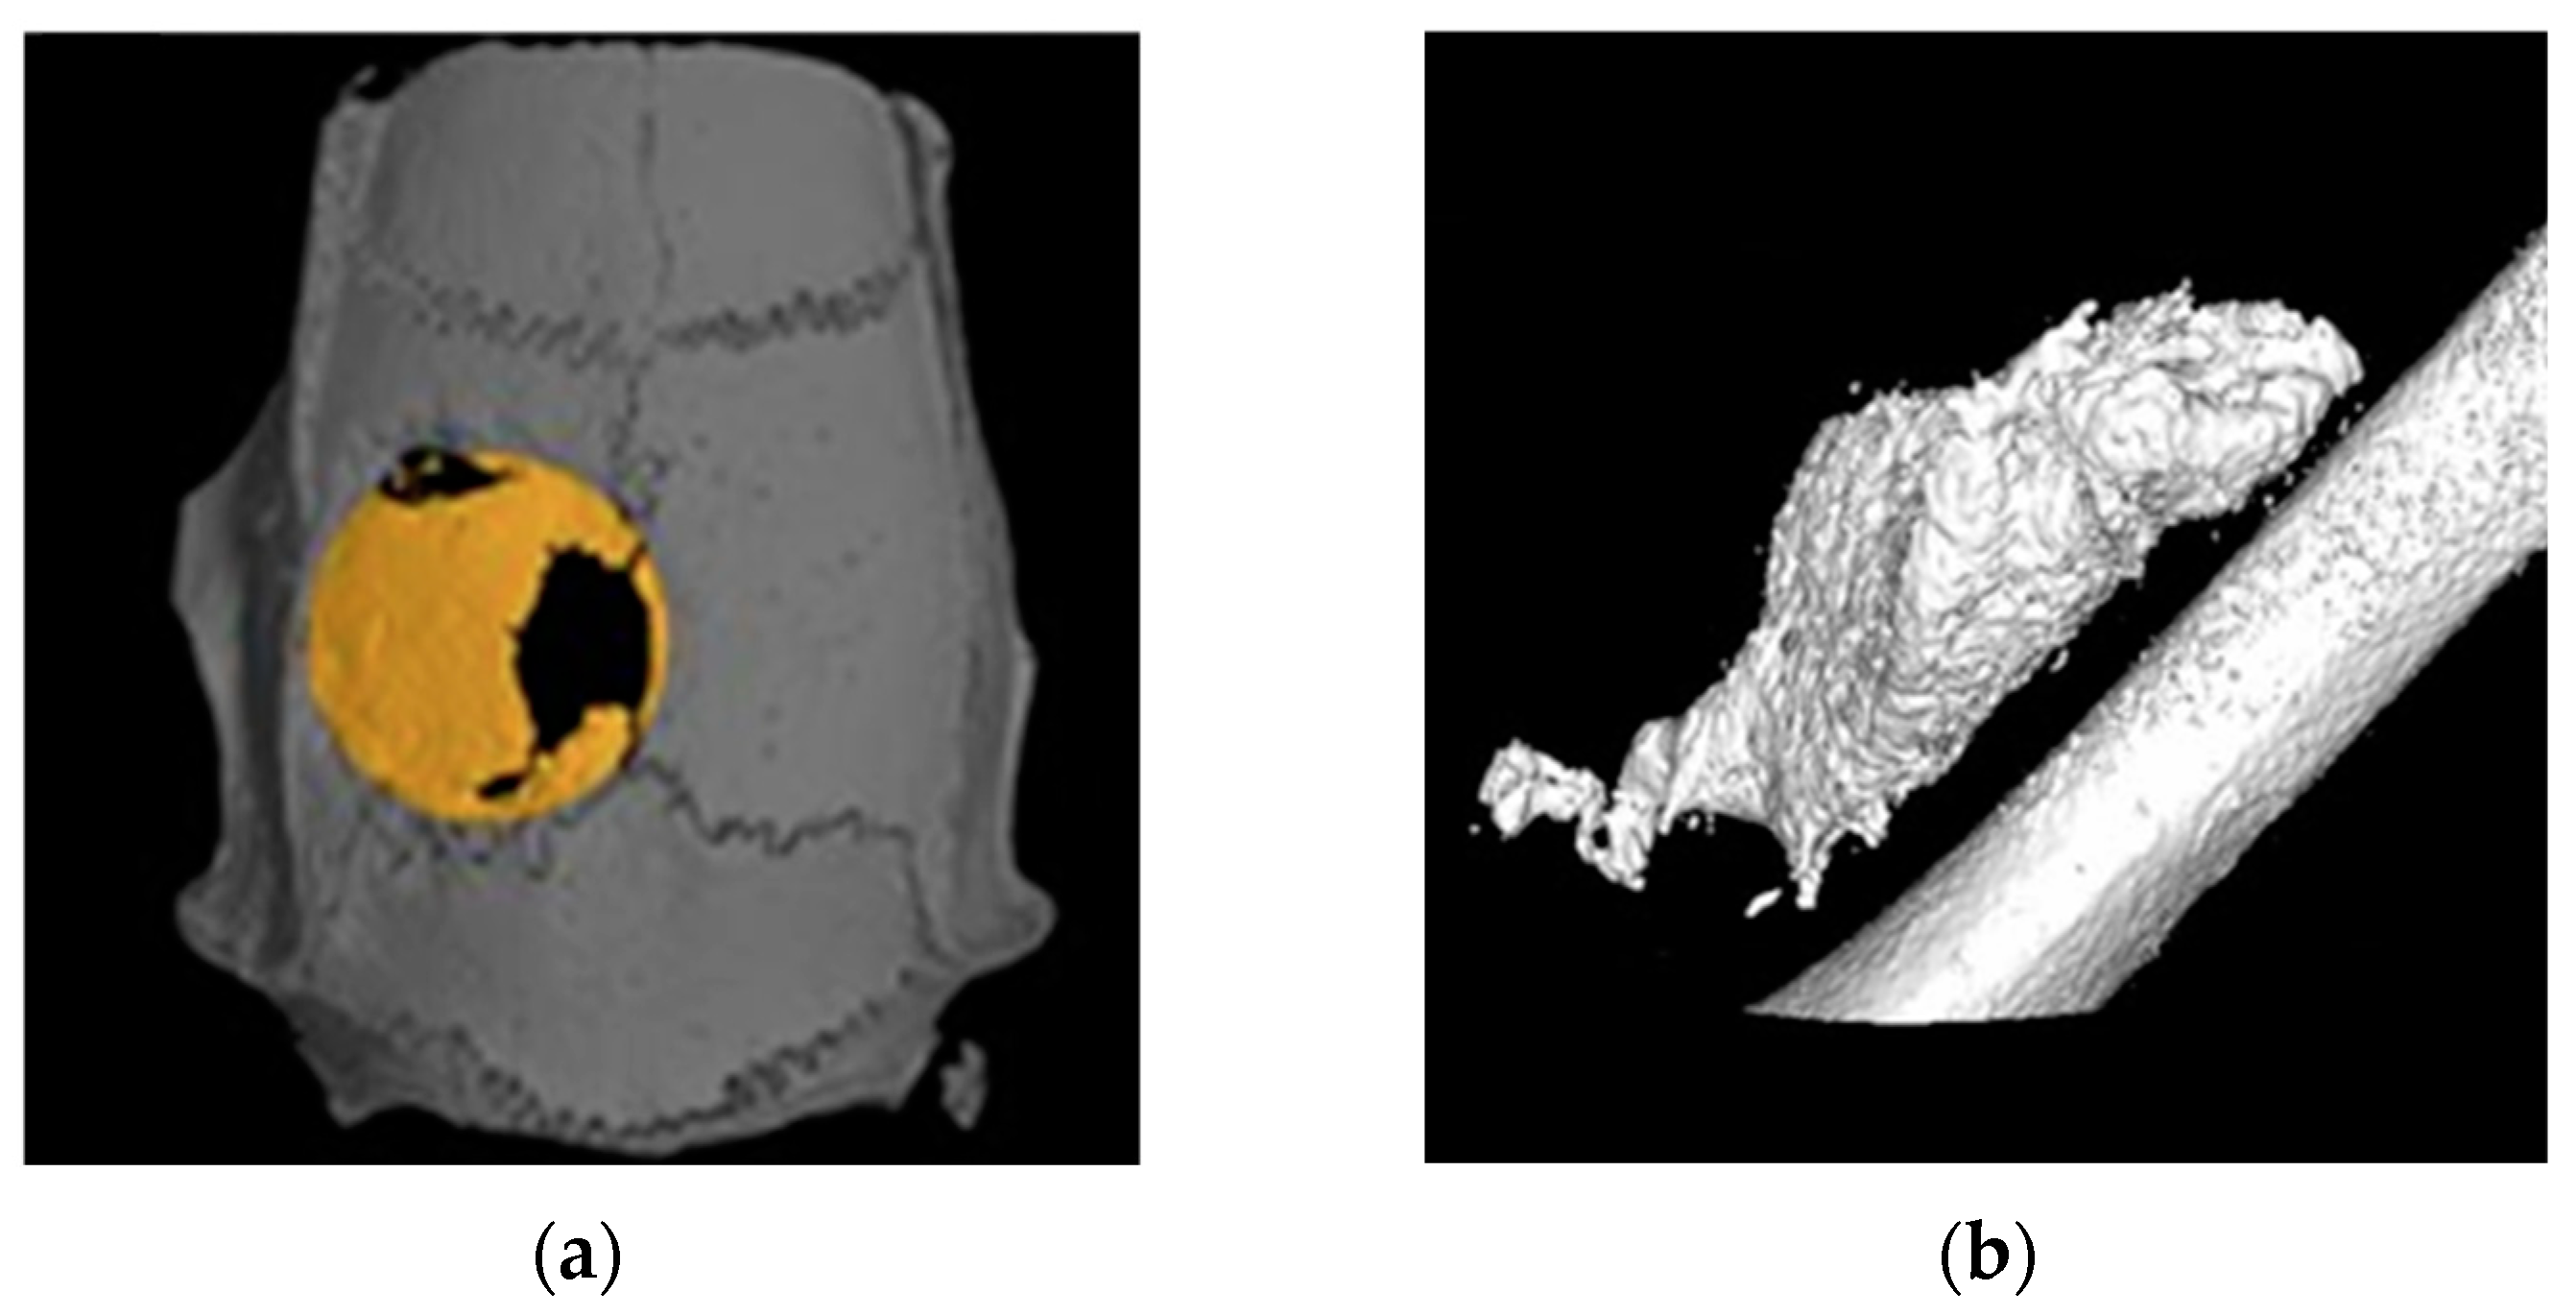

3.2.2. Radiologic Evaluation